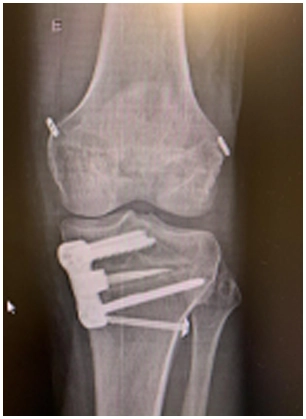

As osteotomias são procedimentos cirúrgicos que envolvem o corte e reposicionamento dos ossos ao redor da articulação do joelho para corrigir deformidades angulares, como a osteoartrose em estágio inicial ou instabilidade ligamentar. Esse procedimento visa redistribuir as forças na articulação do joelho e aliviar a pressão sobre as áreas danificadas da cartilagem.